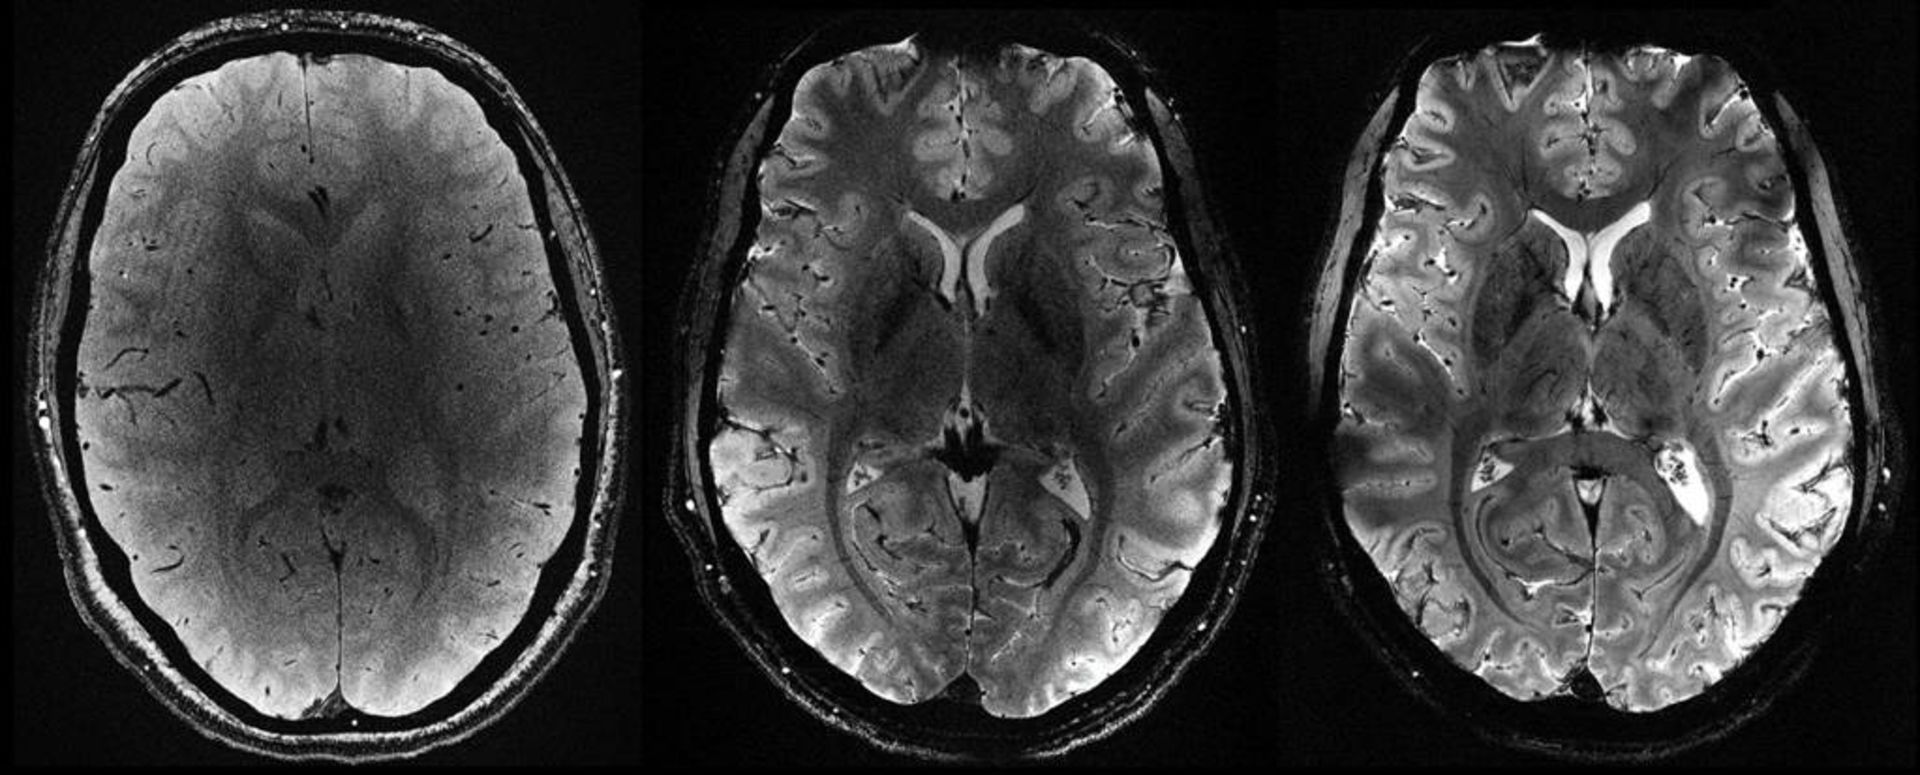

ثبت اولین تصاویر مغز انسان با قدرتمندترین دستگاه MRI جهان

قدرتمندترین اسکنر امآرآی جهان اولین تصاویر خود را از مغز انسان ارائه کرده است. تصاویر حاصل از این دستگاه از دقت بسیار بالایی برخوردار است و پژوهشگران امیدوارند بینشهای جدیدی درباره ذهن ما و بیماریهایی که آن را دچار میکند، فراهم کند.

الکساندر ونگارد، فیزیکدانی که روی پروژه ساخت قدرتمندترین دستگاه MRI جهان کار میکند، میگوید: «شاهد سطحی از دقت بودهایم که قبلا CEA به آن دست پیدا نکرده بود.»

میدان مغناطیسی ایجادشده توسط اسکنر برابر ۱۱٫۷ تسلا است که واحد اندازهگیری به نام مخترع آن نیکولا تسلا است. قدرت بالا به دستگاه جدید این امکان را میدهد که تصاویر را با دقت ۱۰ برابر بیشتر از دستگاههای امآرآی کنونی که در بیمارستانها استفاده میشود، اسکن کند. قدرت دستگاههای امآرآی مرسوم معمولا بیشتر از سه تسلا نمیشود.

ونگارد روی صفحه نمایش کامپیوتر، تصاویر گرفتهشده توسط اسکنر قدرتمند را که Iseult نام دارد، با تصاویر گرفتهشده توسط امآرآی معمولی مقایسه کرد. او گفت: «با این دستگاه میتوان عروق ریزی را که به قشر مغز خون میرسانند یا جزئیات مخچه را مشاهده کرد که تاکنون تقریبا نامرئی بود.»